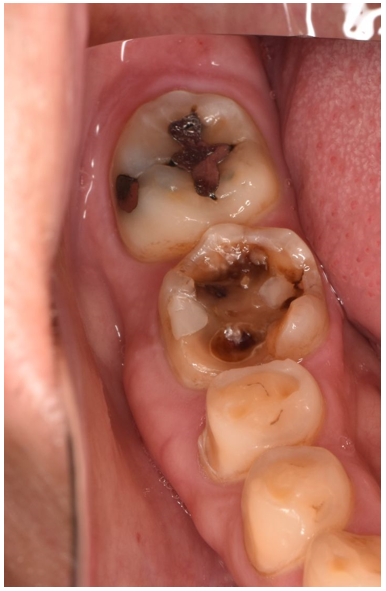

セラミック 2021.0930代女性「虫歯をセラミックで治したい」むし歯治療後にセラミックのインレー・クラウンを使用した症例